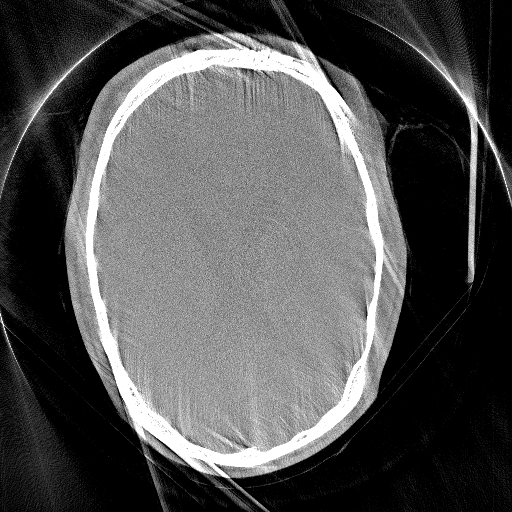

Figure 3 compares the proposed network-based IQM with the entropy-based IQM. The optimization process is identically for both metrics. In an inverse crime scenario both methods can restore the original image quality, however, in a more realistic setting the image entropy is stuck in a local minimum, whereas the network is able to lead the optimization to a nearby motion-free solution.

Refer to captionGt Refer to caption Mo a Refer to captionEnt Refer to captionPro a Refer to captionEnt Refer to caption Pro

Ground Truth (Gt) and Motion Affected Inverse Crime Compensation Clinical Setting (Entropy and Proposed)

Figure 3: Reconstructions of the test patient using [500-2000] HU window. In the inverse crime scenario, the SSIM to the Gt is 0.840.840.84 (Ent/Gt) and 0.950.950.95 (Pro/Gt), respectively for the entropy (Ent) and proposed (Pro) measure. For the more realistic setting (Clinical Setting) the SSIM is 0.650.650.65 (Ent/Gt) and 0.840.840.84 (Pro/Gt), respectively.